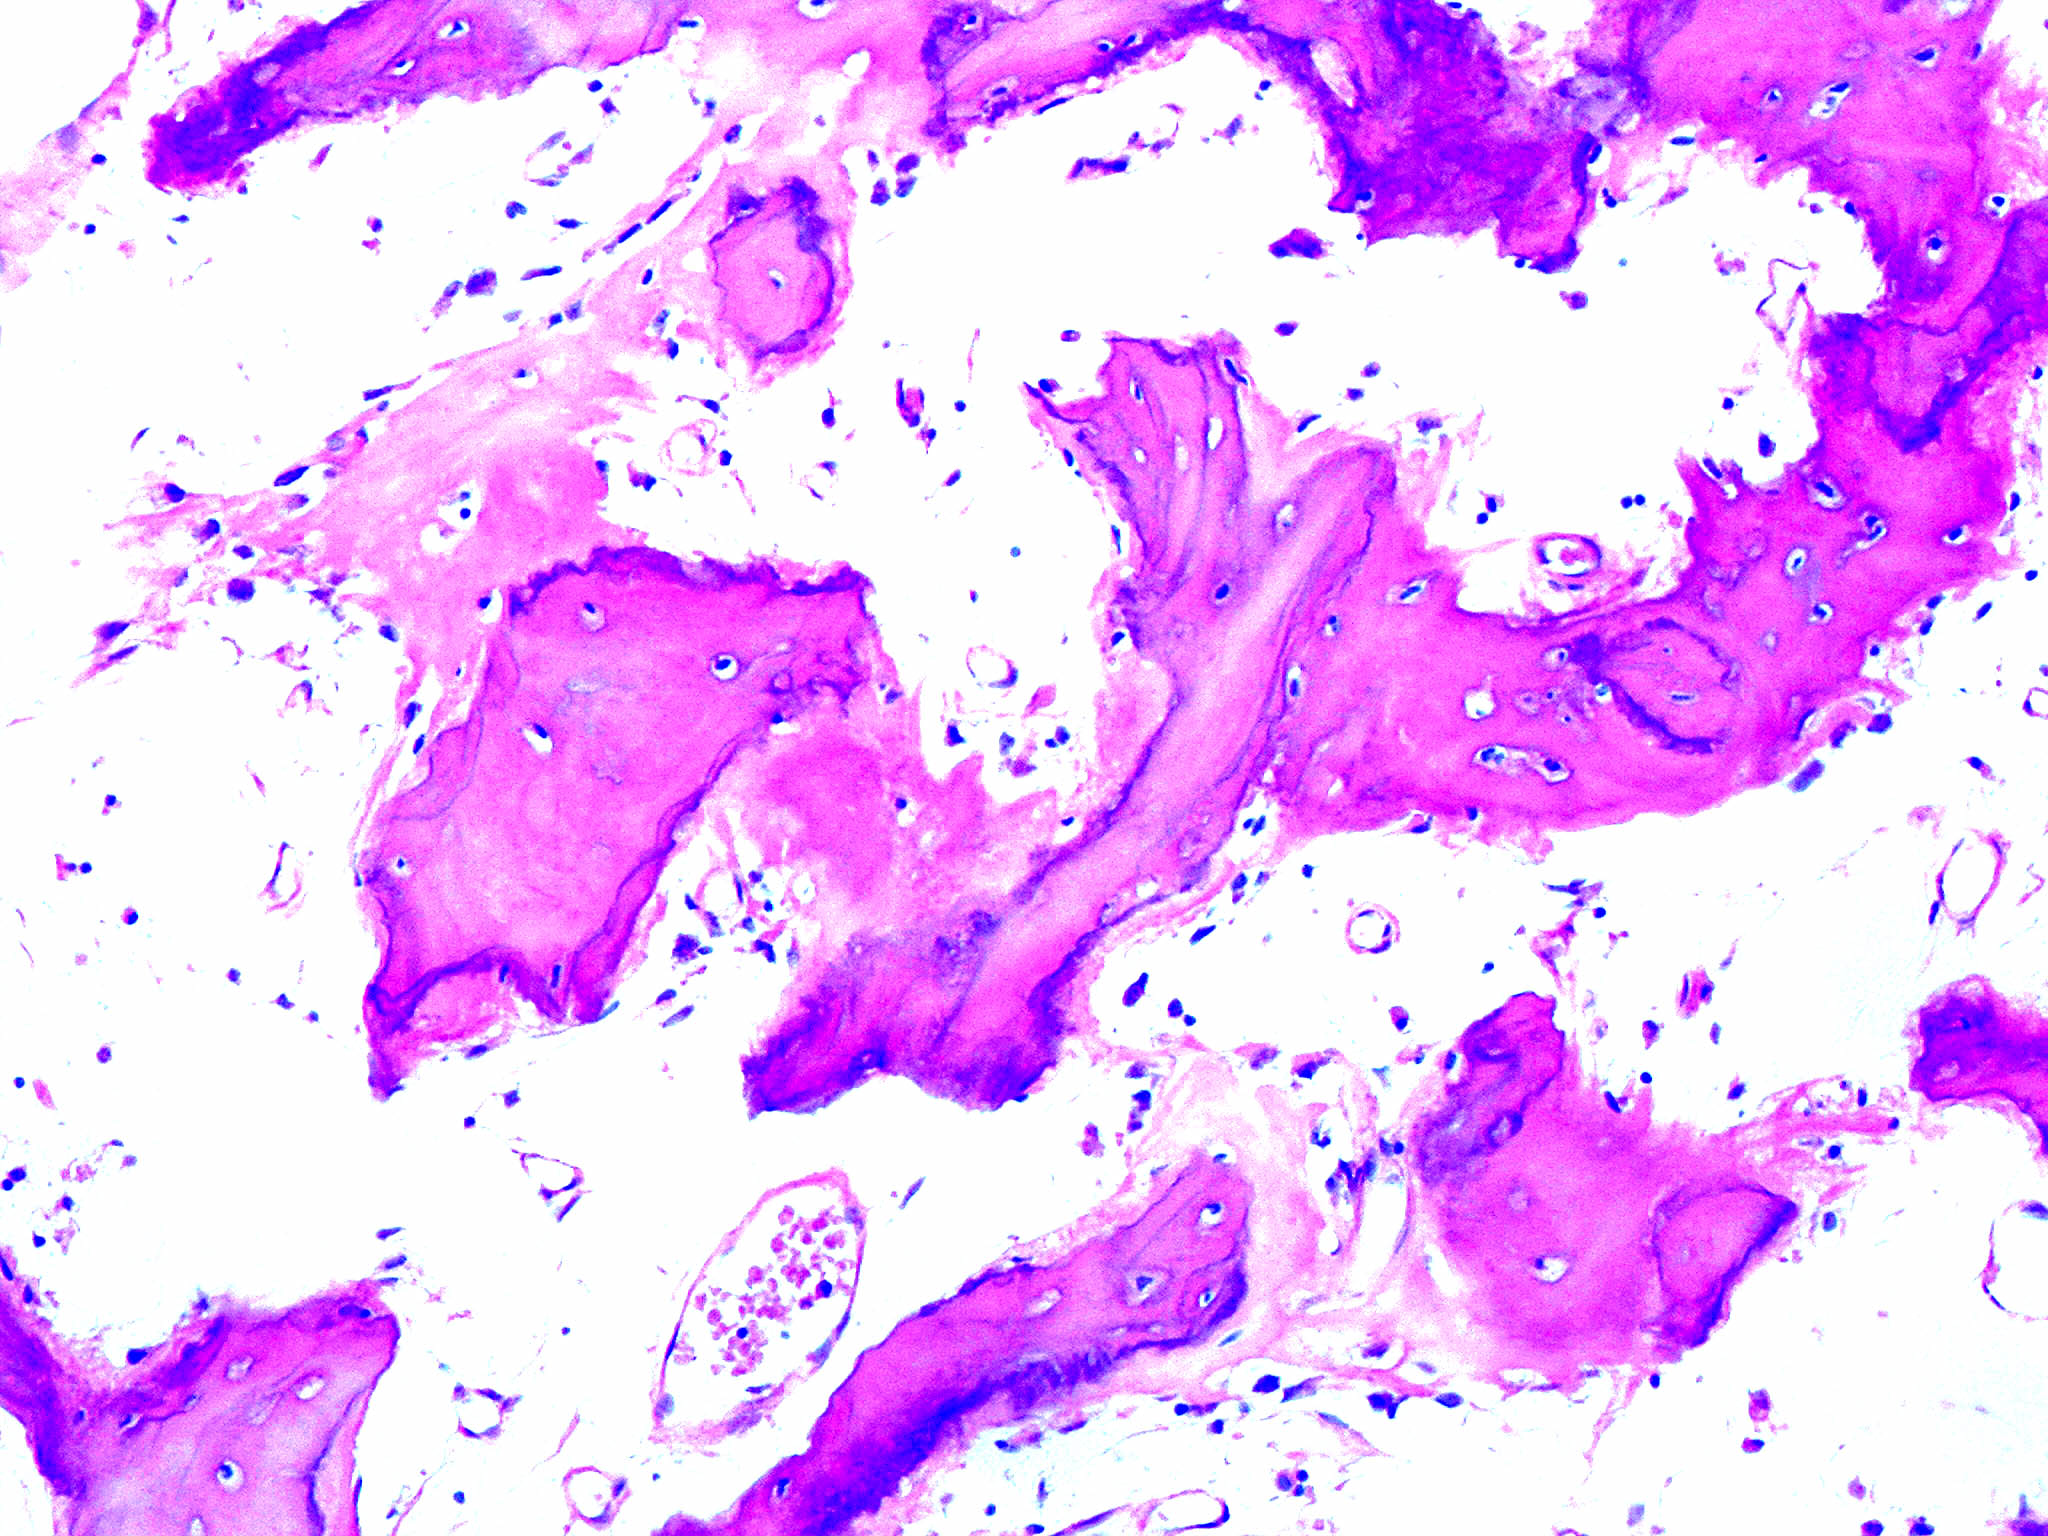

Paget's Disease Ribs . Paget disease is a disorder of increased bone resorption and formation in older persons that leads to thickening and fragility of the affected bones. Paget disease is the second most common bone disease after osteoporosis that affects elderly persons in the united states. We revisit paget disease of bone and present the gamut of imaging findings associated with this skeletal disorder, both uncomplicated and complicated. Paget's disease is an idiopathic condition of abnormal bone remodeling with normal bone being replaced through an active interplay between excessive bone resorption and abnormal new. When paget’s disease puts strain on joints it can lead to damage (osteoarthritis) and if pain and disability from this become severe, joint. Paget disease, right 6th rib. The symptoms of paget’s disease vary widely. In many cases, individuals are unaware that they. Many people who have paget’s disease do not have symptoms and never develop complications. The cortex is thickened (white arrows) but the medullary space remains intact (red arrow) with no evidence.

Paget disease, right 6th rib. When paget’s disease puts strain on joints it can lead to damage (osteoarthritis) and if pain and disability from this become severe, joint. The symptoms of paget’s disease vary widely. Paget disease is a disorder of increased bone resorption and formation in older persons that leads to thickening and fragility of the affected bones. We revisit paget disease of bone and present the gamut of imaging findings associated with this skeletal disorder, both uncomplicated and complicated. The cortex is thickened (white arrows) but the medullary space remains intact (red arrow) with no evidence. Paget disease is the second most common bone disease after osteoporosis that affects elderly persons in the united states. In many cases, individuals are unaware that they. Paget's disease is an idiopathic condition of abnormal bone remodeling with normal bone being replaced through an active interplay between excessive bone resorption and abnormal new. Many people who have paget’s disease do not have symptoms and never develop complications.